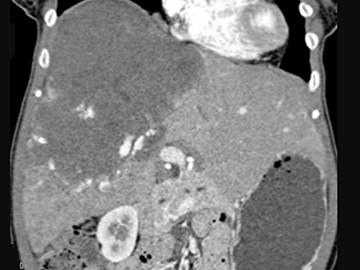

女,34岁,右上腹胀痛不适,肝肋下3cm,CT所见如图,最可能的诊断是()

• A.原发性肝癌

• B.肝海绵状血管瘤

• C.肝腺瘤

• D.肝局灶性结节增生

• E.肝脓肿